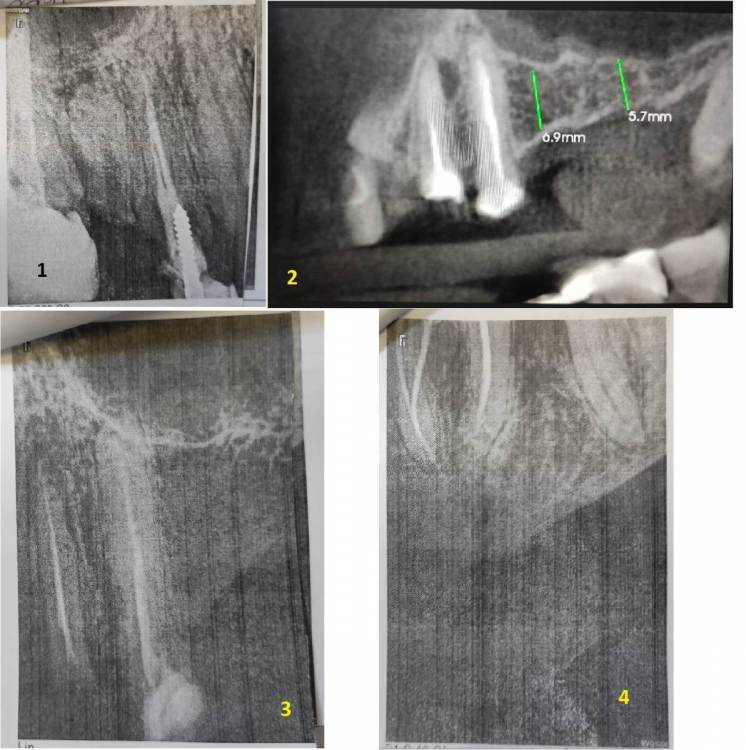

ЕвгенийПет Опубликовано 30 ноября, 2023 Поделиться Опубликовано 30 ноября, 2023 (изменено) Доброго дня! Уважаемые врачи, проблема и вопросы у меня в следующем: Примерно в 2010 году пришлось удалить 26 и 27 зубы (сначала свищ на одном, а со временем (около года) уже не помню почему и второй. С тех пор жую только на правую сторону, а сейчас под удаление 15 (снимок №1 во вложении), весной отекло лицо, обнаружили гранулему и вскрывали абсцесс. Тоже вопрос, хотя даже я по снимку вижу, что его не спасти, но а вдруг? Так вот, с жеванием теперь возникнут явные проблемы (отсутствует 46 зуб), и нужно срочно что-то решить со вторым рядом. Сразу скажу, что импланты сейчас не могу себе позволить, так как в прошлом году делал КТ, показывал хирургу, он сказал, что там перфорация и обязательно нужен синус-лифтинг (снимок №2 во вложении). Посмотрите, пожалуйста, это реально так? Без синус-лифтинга точно никак? Основной вопрос (снимок №3 вчера сделал) - врач предлагает сделать консольный мост с тремя коронками - с вкладкой на 24, закрыть 25 и созданный 26. Сразу скажу, что прошлым летом перелечивал канал в 24 и ставил на него металлокерамику на двух штифтах (один уже был ранее, второй добавили), но она сломалась месяц назад, чуть более года (из-за этого у меня вообще недоверие к коронкам, у меня 35 зуб только корень, на нем сделана пломба, и он стоит уже 7 лет без проблем). Первый основной вопрос - хорошо ли пролечены каналы в 24 и 25 зубах под мост? И второй основной вопрос - насколько будет прочна конструкция консольного моста, с учетом отсутствия 27? какие риски продолжения разъезжания ряда (за эти 14 лет эта сторона и так уже прилично разъехалась)? Момент еще в том, что сильно выросли за это время 36 и 37 зубы, там буквально милиметр остается для новых 26 и 27 зубов. Ранее другой врач мне советовал сделать мост с опорами на 28 и 24+25, но текущий врач такое даже не рассматривает, говорит, что 28 кривой уже (не депульпирован) и такая конструкция сломается быстро, а консольный 24+25+26 будет надежнее. Прошу помощи и консультации, что можно сделать в данной ситуации кроме имплантов. Заранее благодарю! И менее важный вопрос - позавчера депульпировал 36 зуб, посмотрите, пожалуйста (снимок №4), хорошо ли пролечены каналы? Спасибо! Изменено 30 ноября, 2023 пользователем ЕвгенийПет Ссылка на комментарий

red_butler Опубликовано 5 декабря, 2023 Поделиться Опубликовано 5 декабря, 2023 30.11.2023 в 14:16, ЕвгенийПет сказал: Первый основной вопрос - хорошо ли пролечены каналы в 24 и 25 зубах под мост? нет 30.11.2023 в 14:16, ЕвгенийПет сказал: И второй основной вопрос - насколько будет прочна конструкция консольного моста, с учетом отсутствия 27 не прочная, потеряете опорные зубы. 30.11.2023 в 14:16, ЕвгенийПет сказал: Сразу скажу, что импланты сейчас не могу себе позволить, так как в прошлом году делал КТ, показывал хирургу, он сказал, что там перфорация и обязательно нужен синус-лифтинг покажите еще срезы Кт, ничего критичного не вижу. 30.11.2023 в 14:16, ЕвгенийПет сказал: Прошу помощи и консультации, что можно сделать в данной ситуации кроме имплантов. Частично съемный протез 1 Ссылка на комментарий

ЕвгенийПет Опубликовано 6 декабря, 2023 Автор Поделиться Опубликовано 6 декабря, 2023 @red_butler Спасибо большое! Понял, консольный делать не буду. КТ приложил. КТ Петров.rar Ссылка на комментарий